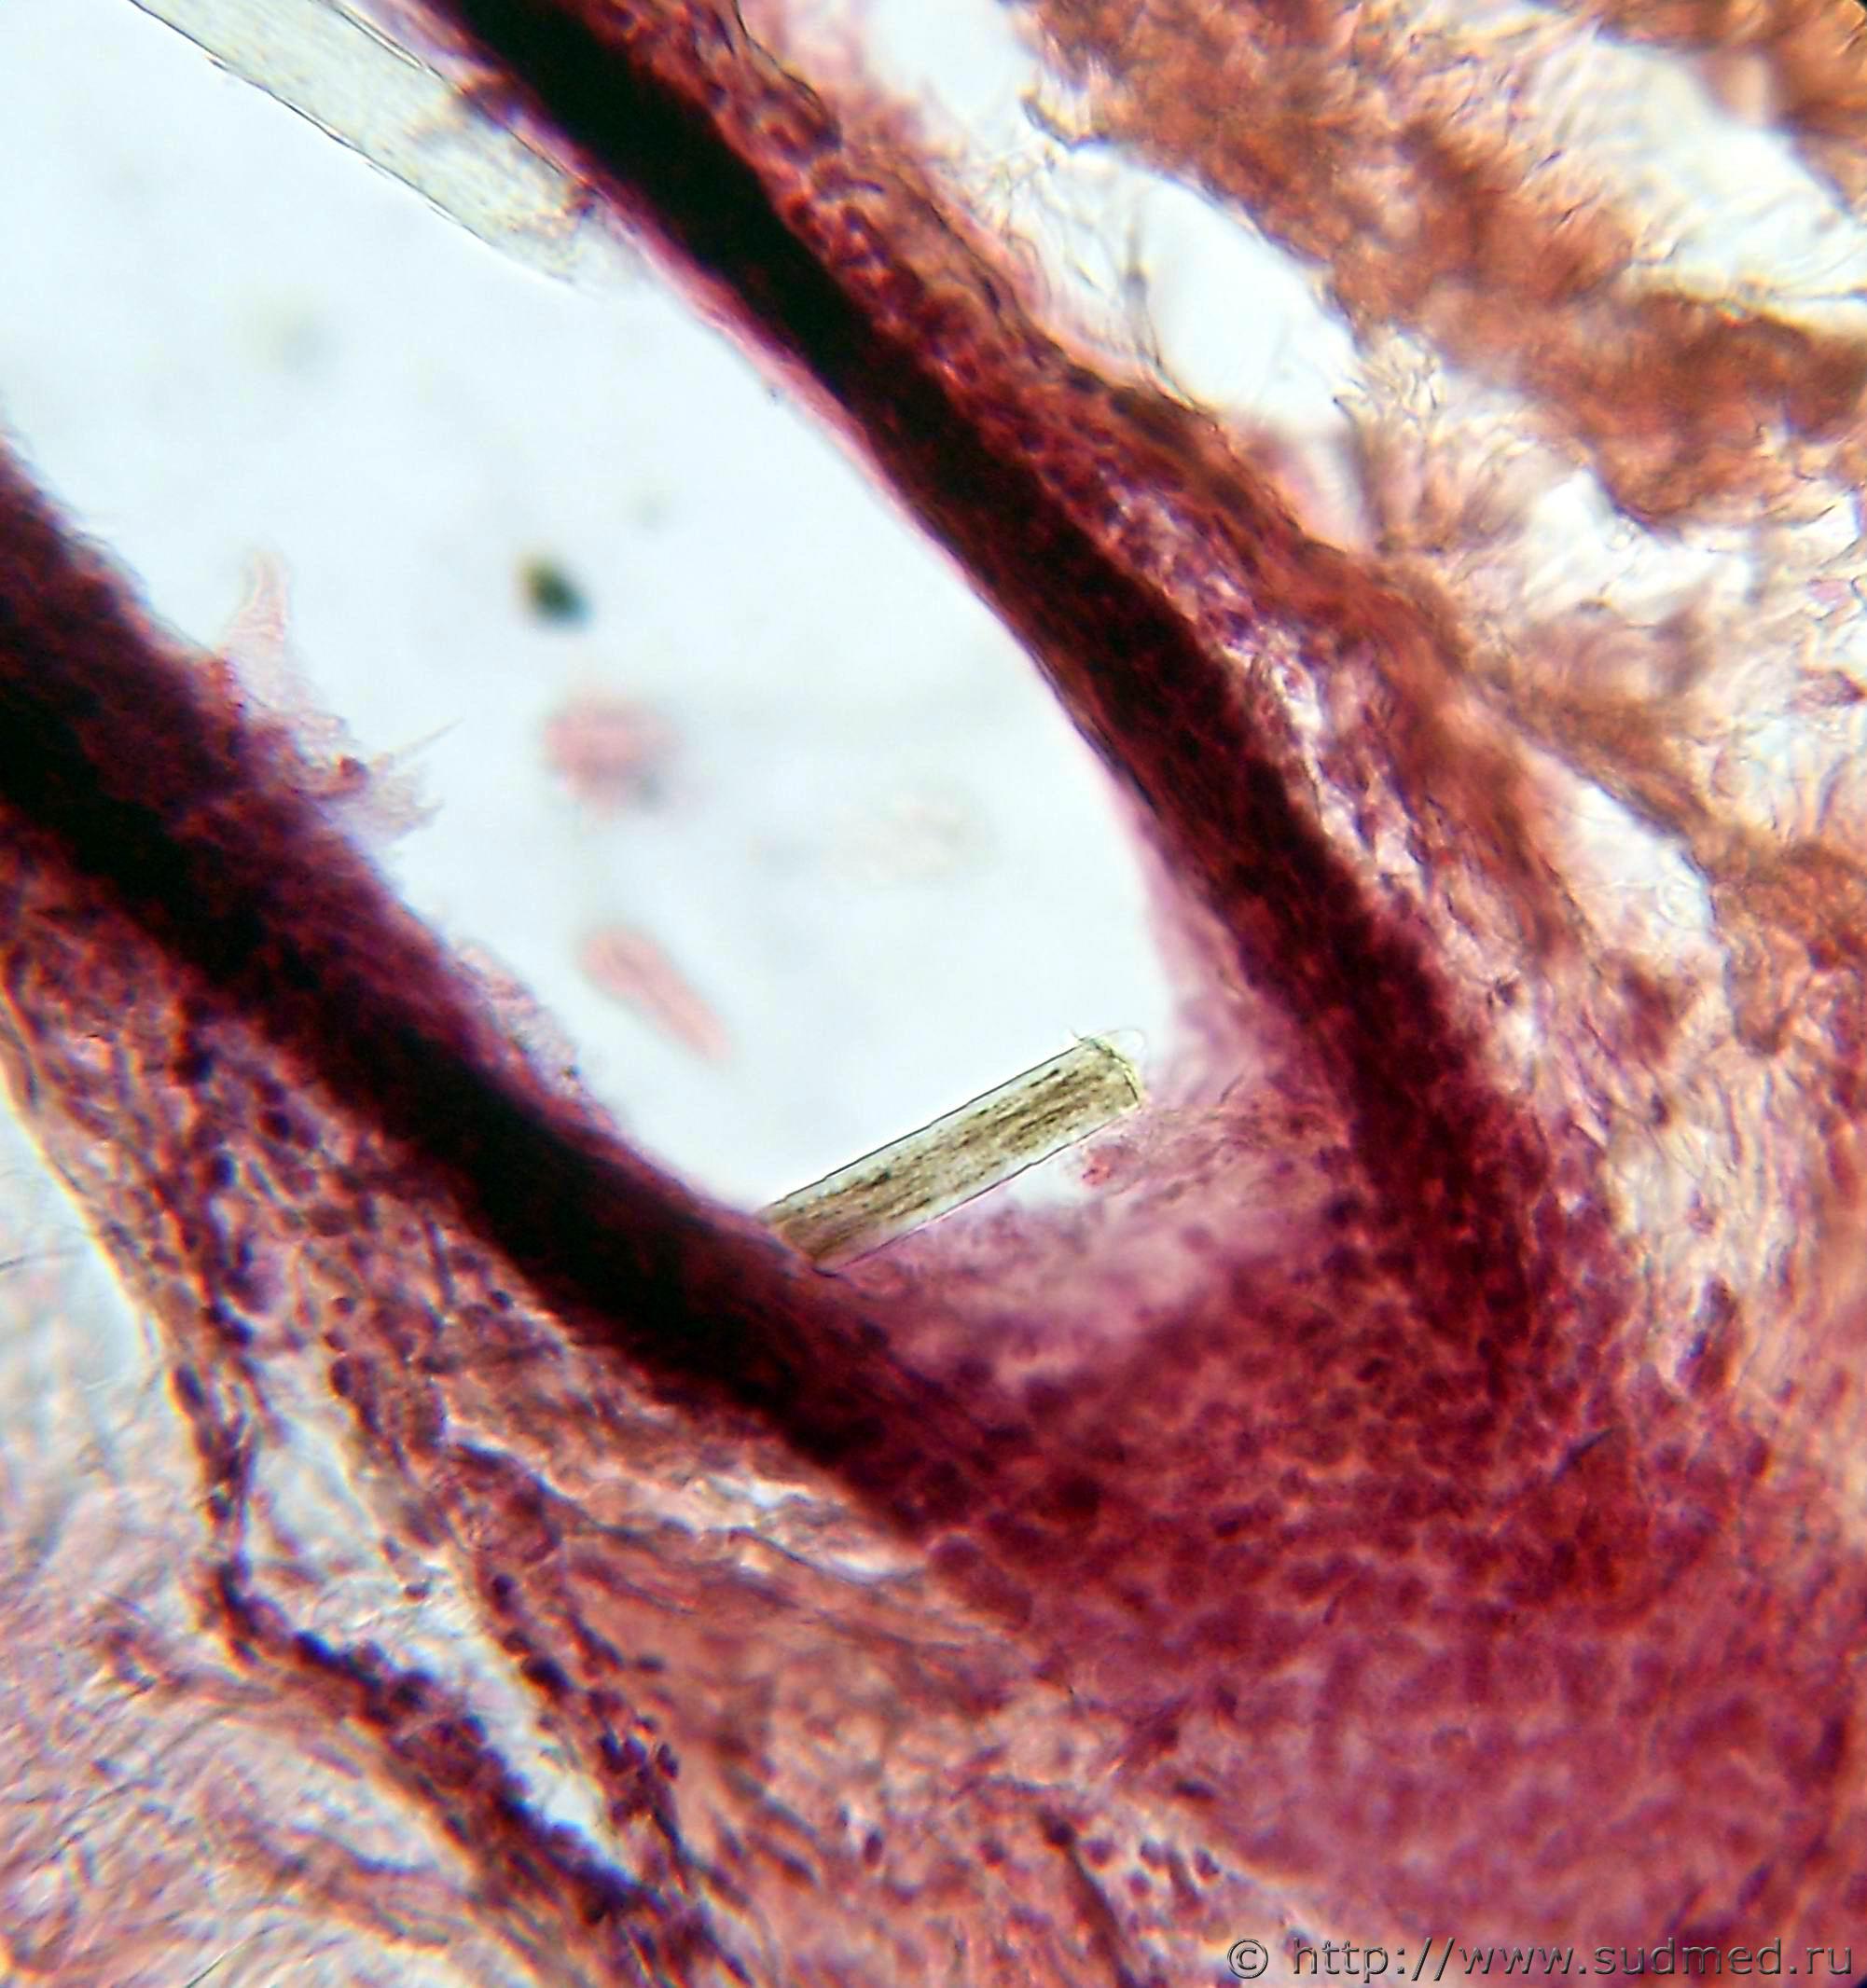

фото 1. металлизация электрометки. Встречается довольно редко (по крайней мере мне)

фото 2. Наличие волоса в странгуляционной борозде. Интересно установить групповую принадлежность данного волоса (вдруг он не принадлежит умершему)